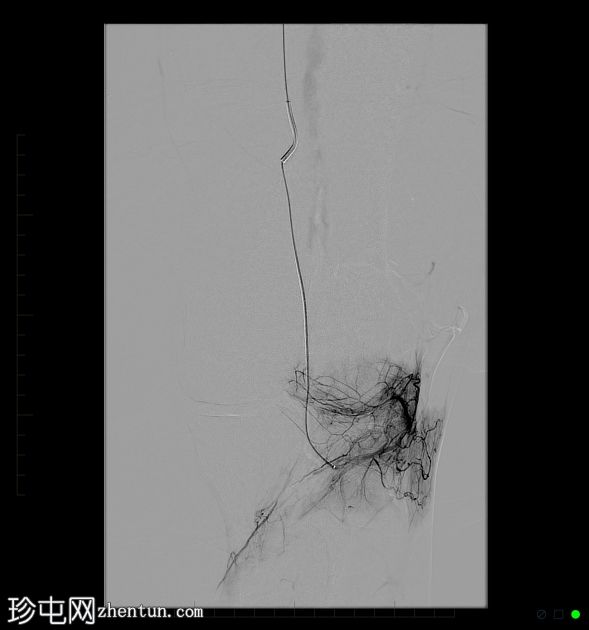

栓塞术前选择性血管造影显示,股骨外侧髁和胫骨平台滑膜充血明显异常。

栓塞术后选择性血管造影显示,异常充血消退(“血管修剪”),同时保留了主要的滑膜动脉供血(膝骨外侧上动脉和膝骨外侧下动脉)。

经股动脉建立动脉通路,并进行膝关节诊断性血管造影。结果显示,膝关节外侧髁和胫骨平台供血的异常高血管分支。

随后对异常充血区域进行选择性栓塞,直至达到满意的血管闭塞(“血管修剪”)。